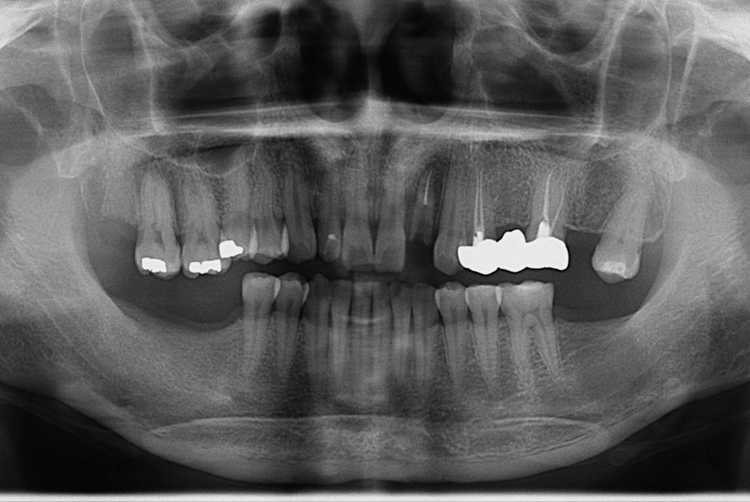

[임플란트] 앞니 임플란트

치료전 : 2018-06-13